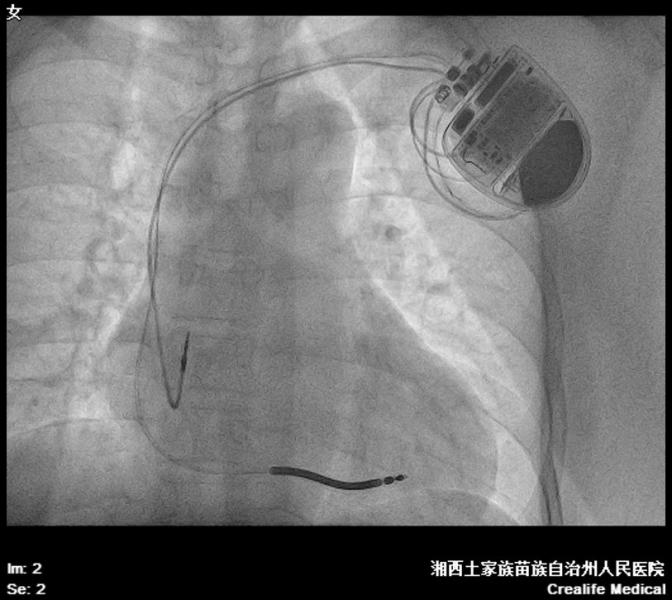

磁共振兼容双腔ICD植入术后       据心内三科主任田鑫介绍,ICD除了基本的起搏功能外,最重要的是当患者发生快速型恶性心律失常时,可迅速识别并给予有效的电击治疗,从而使患者恢复正常心律、转危为安,是预防高危人群心源性猝死的有效手段。

磁共振兼容双腔ICD植入术后